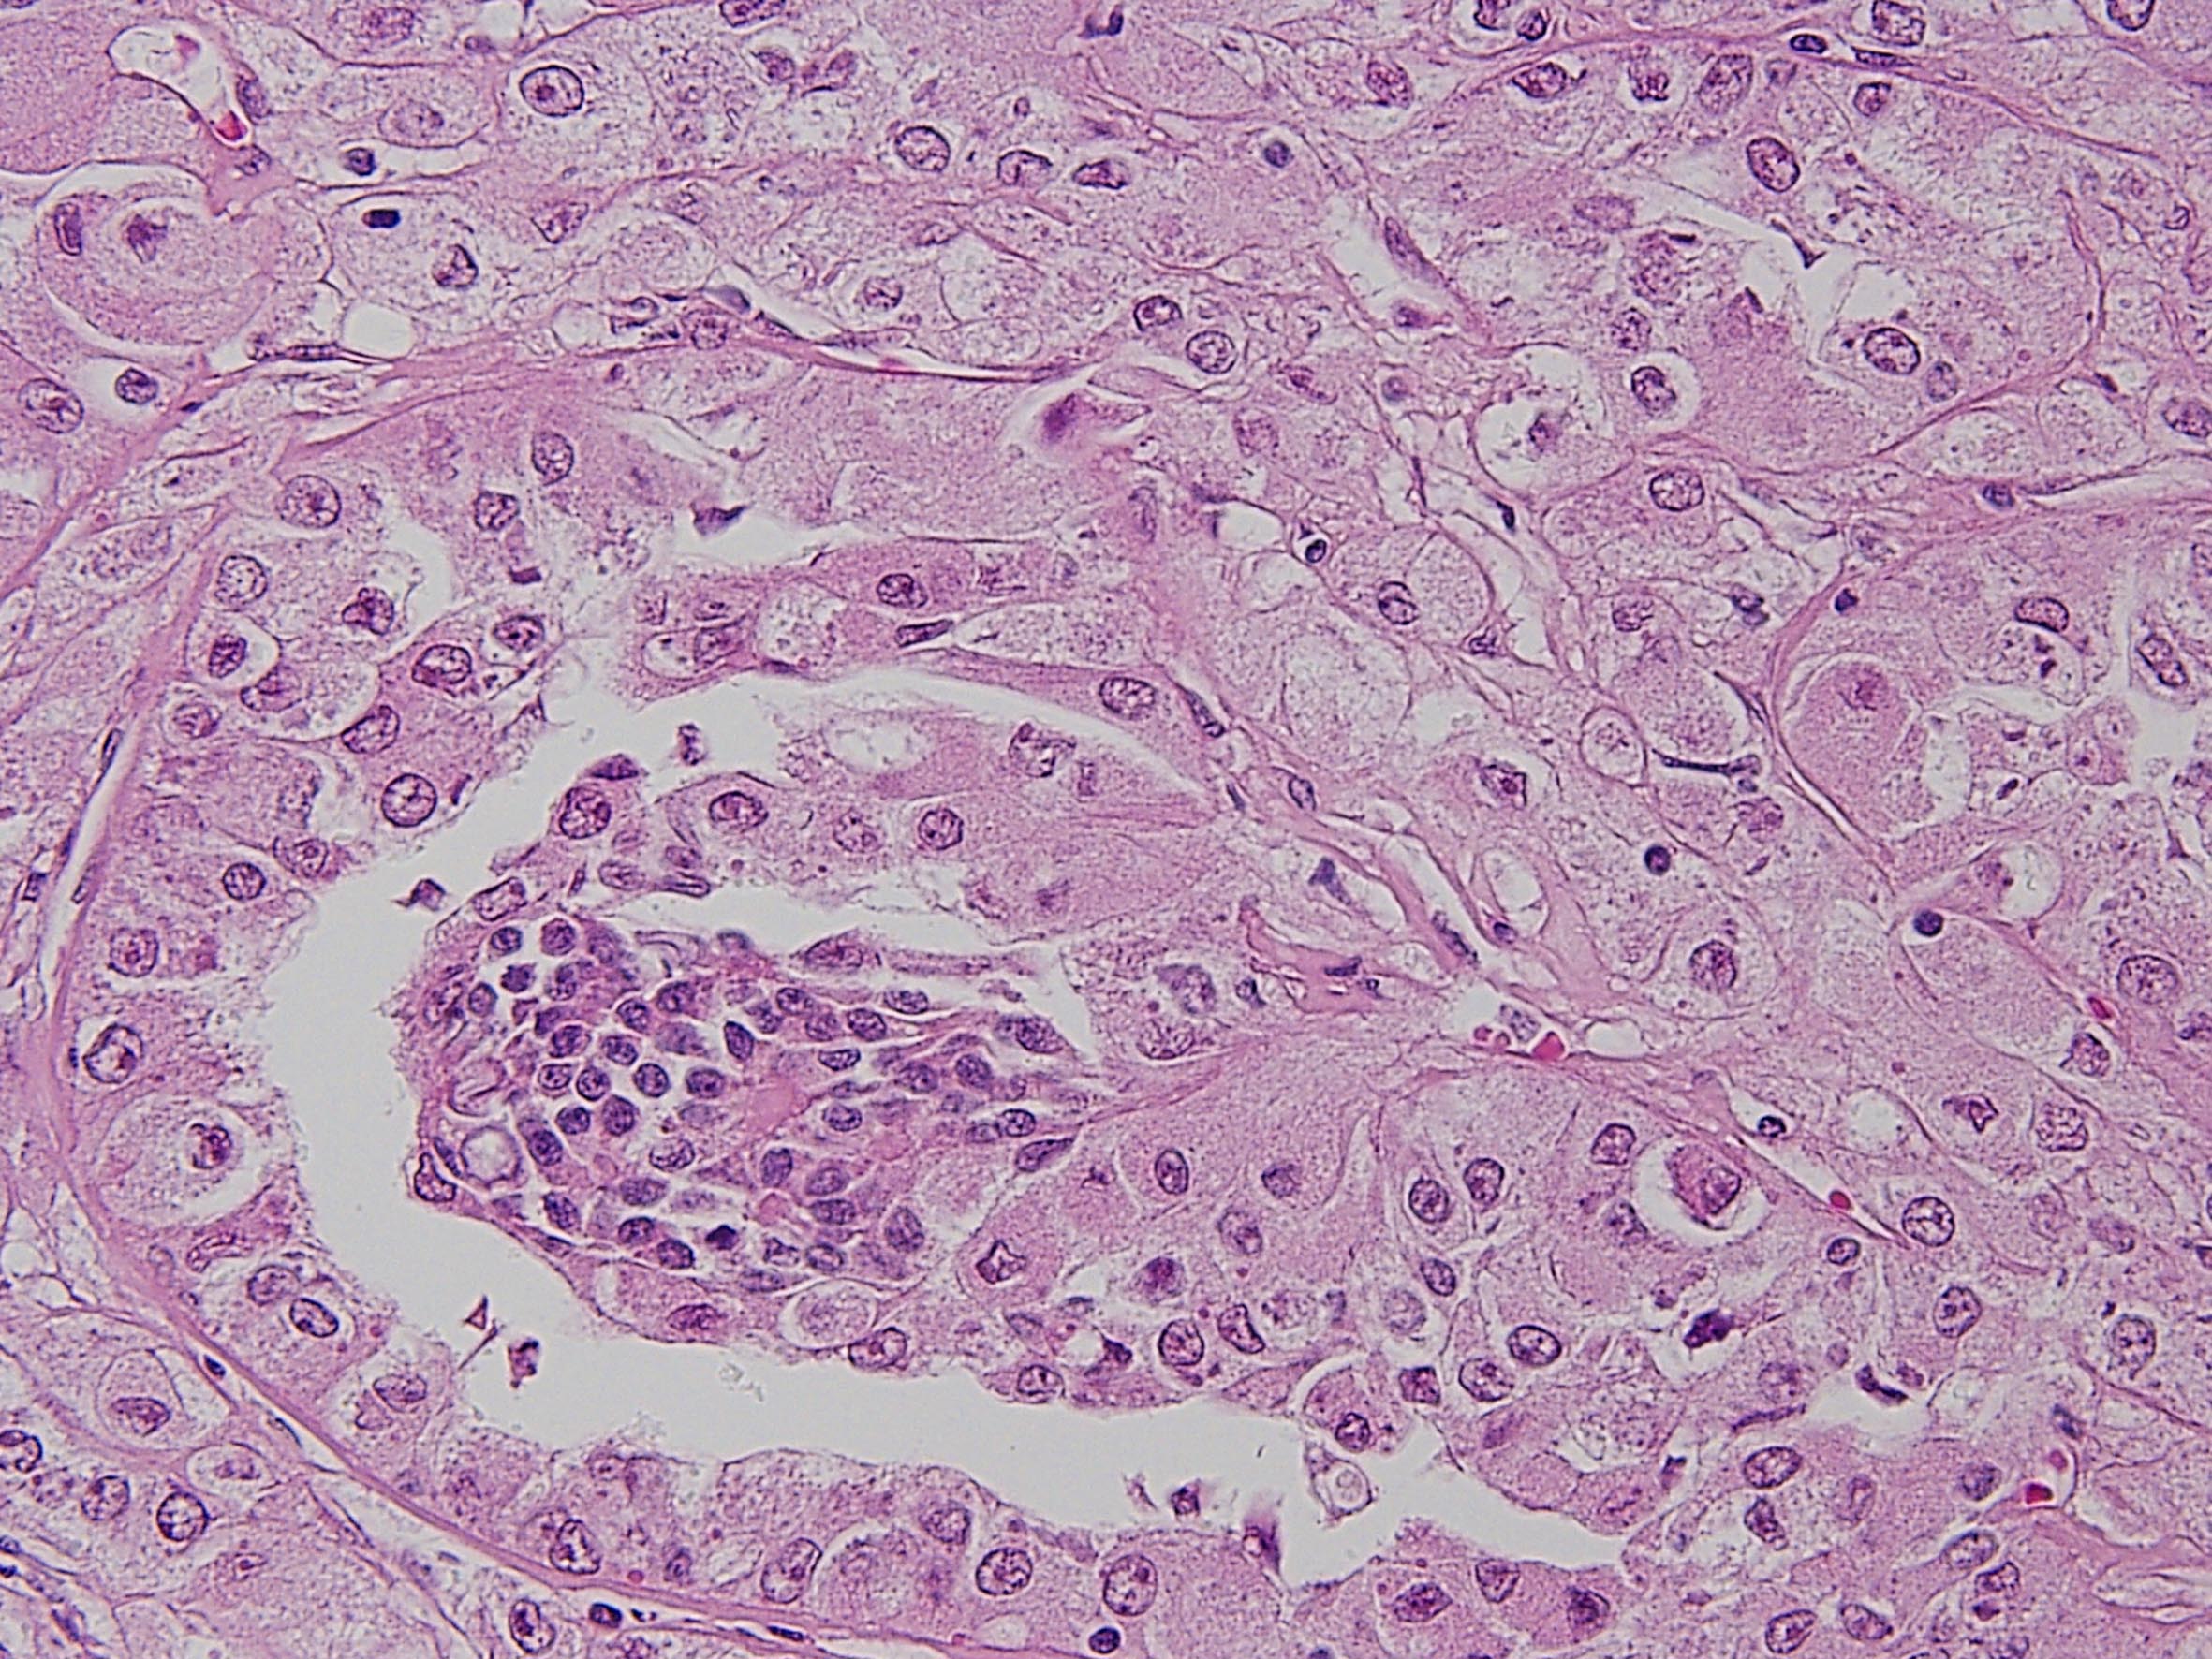

Consensus grade: MiT Family translocation carcinoma

MiT family translocation renal cell carcinoma. t(6;11) translocation

Section courtesy of Dr P Argani